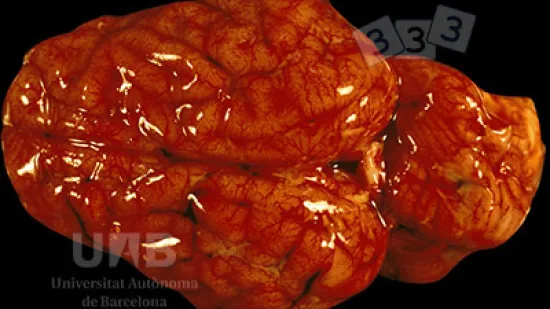

Semaine du 21-Fév-2022

Quelle est cette lésion sur une truie reproductrice qui vient de mourir ?